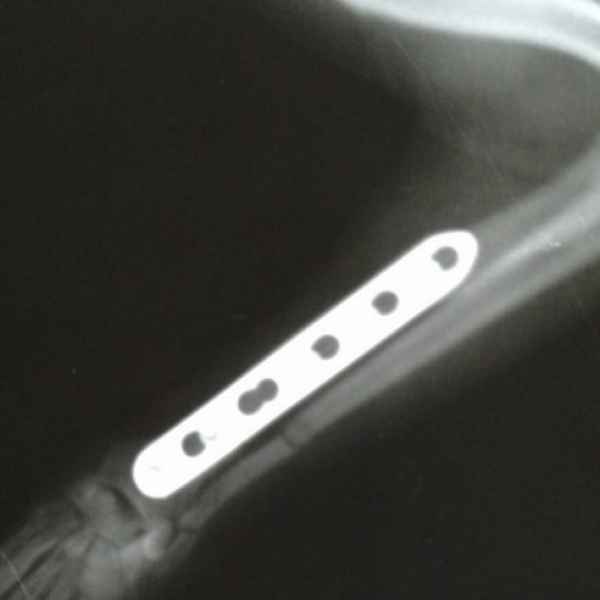

Вот что значит неудачно спрыгнуть с дивана. Это рентгеновские снимки одного из наших пациентов. Сначала хозяева обратили внимание на хромоту, а потом поняли, что у питомца очень болит лапа. Ещё бы не болело - поперечный перелом костей предплечья. Операция, установка DCP-пластины, восстановление, и он снова активный и жизнерадостный.

Этот пациент поступил к нам с кусаной раной левой грудной конечности После рентгенологического исследования обнаружили перелом костей предплечья. Сложность операции заключалось в том, что дистальный отросток лучевой кости был очень коротким. Хирургом нашей клиники было принято решение установить блокируемую lcp пластину. В данный момент пациент полностью восстановился..